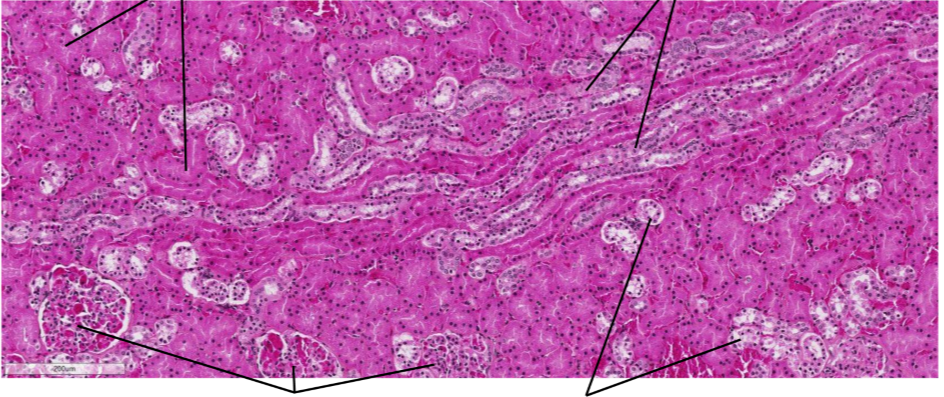

Lame du rein, niveau du cortex HES

Tube contourné proximal (plus foncé parce qu’il a des microvillosité pour réabsorption)

Tube collecteur (moyen foncé)

Corpuscule rénal

tube contourné distal (absence de microvilosité) le moins foncé